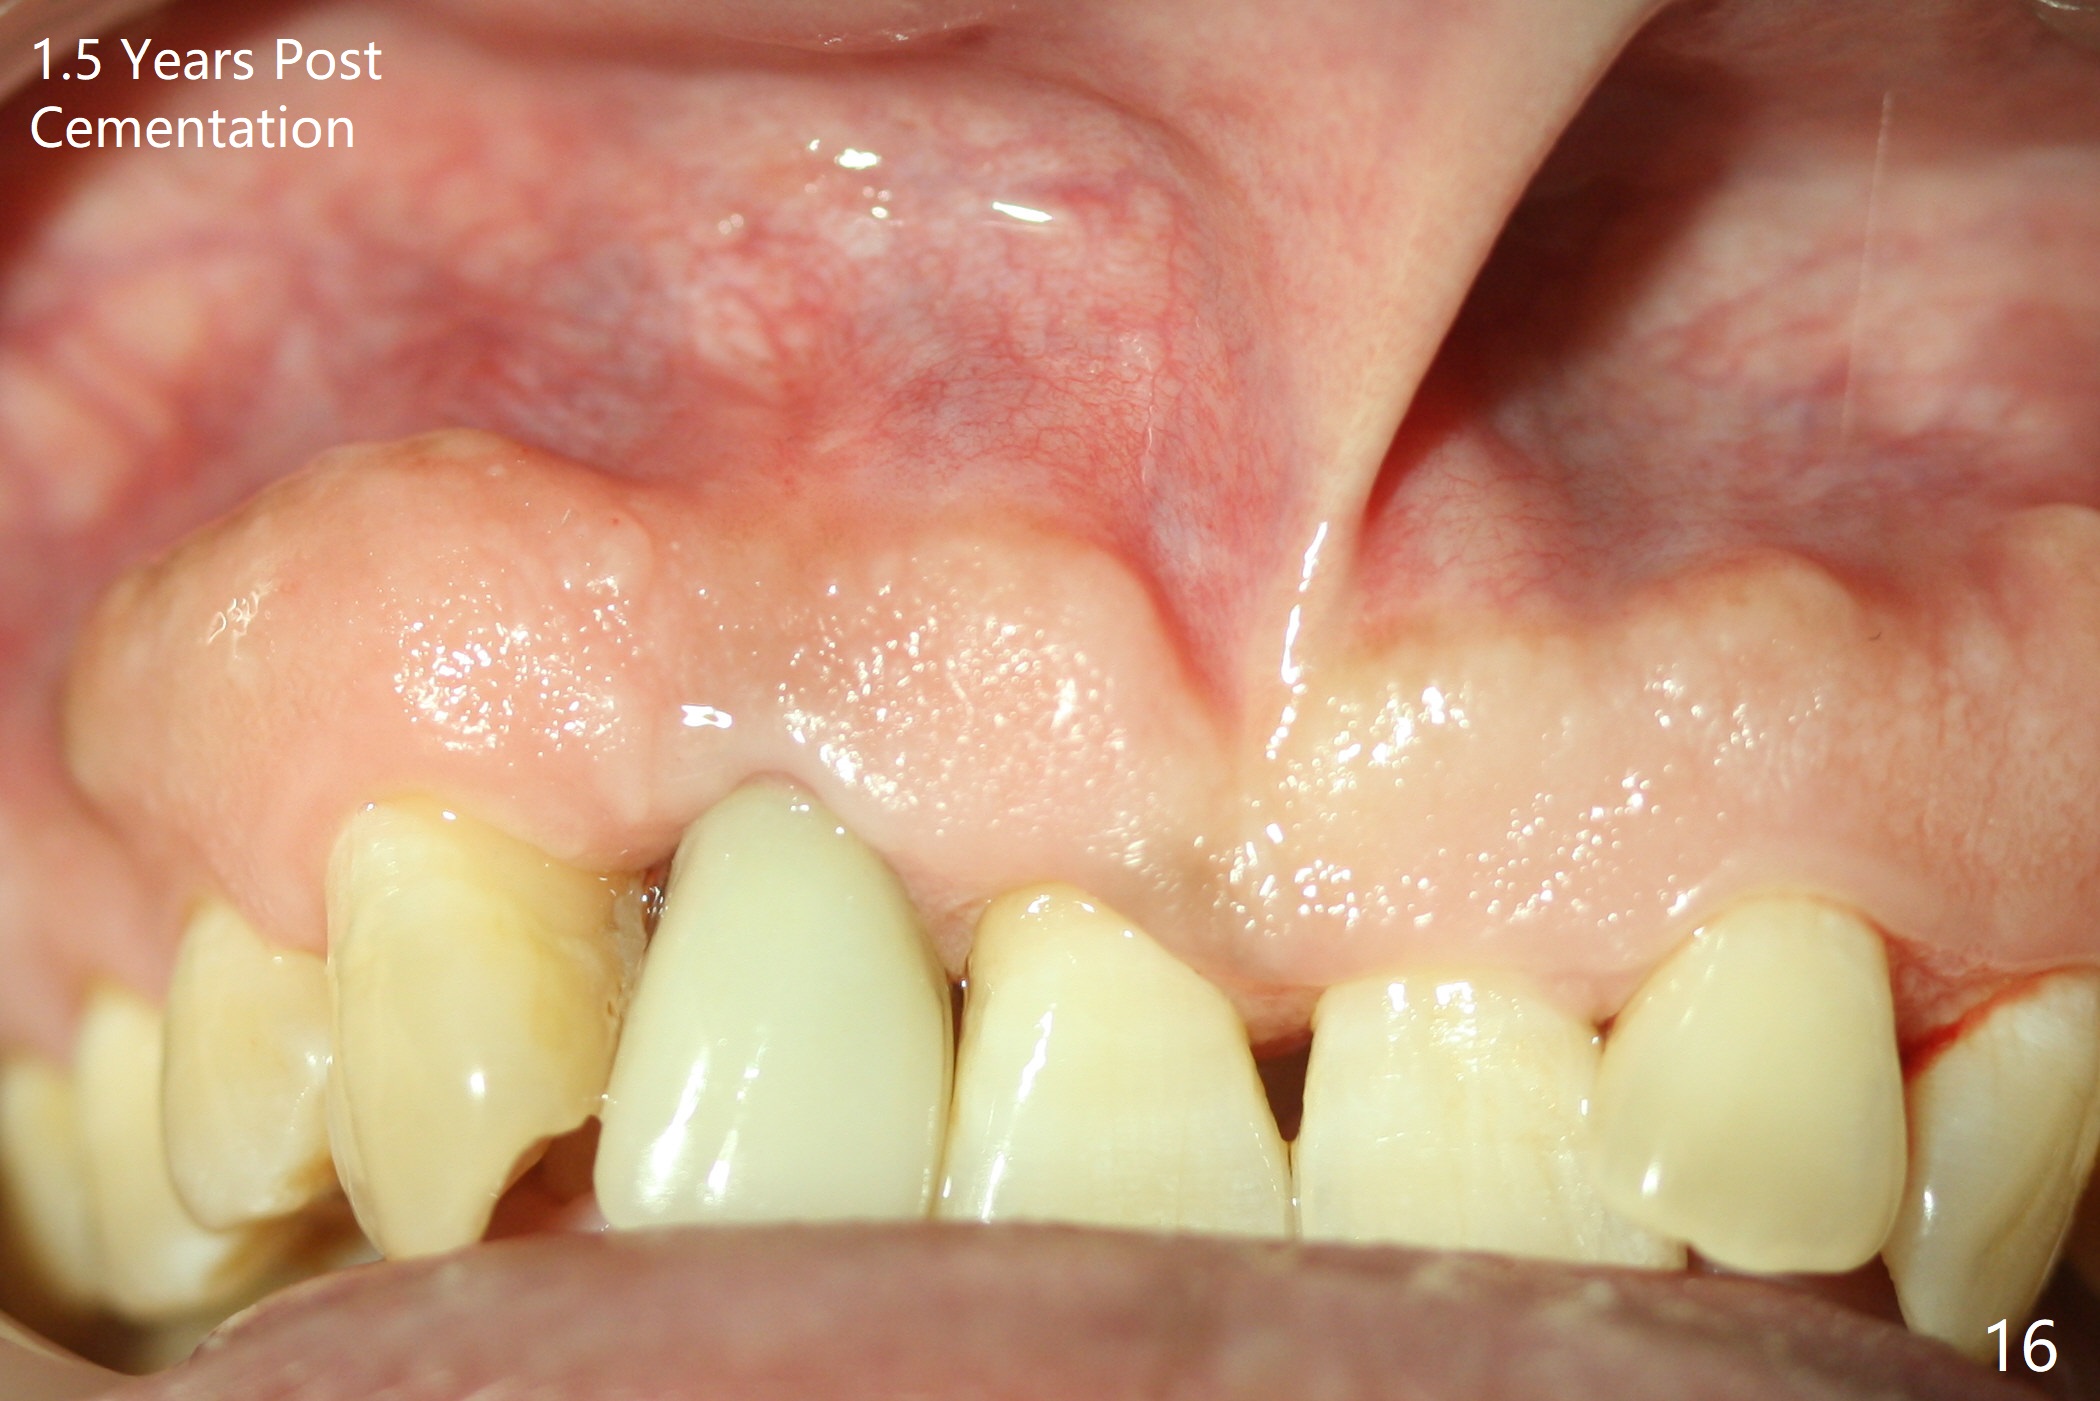

Sixteen days postop, the patient is doing fine, although the labial fistula has not disappeared (Fig.8 <). The detached distolabial papilla is healing (Fig.9 *) with mild bone graft exposure (^). The lacerated distopalatal papilla is also healing (Fig.10 *). These complications are related to flap surgery. The apical portion of the socket appears to have reduced 4 months postop (Fig.14). When the definitive restoration is delivered 5 months postop, there is gingival recession, including the distal of #8 (Fig.11 arrows, which is expected to improve over time) due to flap surgery. The labial plate collapse is minimal (Fig.12 *), while the palatal laceration (Fig.10) has healed (Fig.13). When the patient returns 1.5 years post cementation, there is increased bone density next to the coronal portion of the implant, equivalent to the bone graft (Fig.15 *). The fistula is absent (Fig.16). The crestal bone loss remains 2.5 years post cementation (Fig.17 *), although there is no sign of periimplantitis (magnification). Oral hygiene is poor. There is no change in the soft (gingival recession; data not shown) or hard tissues 3 years 8 months post cementation (Fig.18).